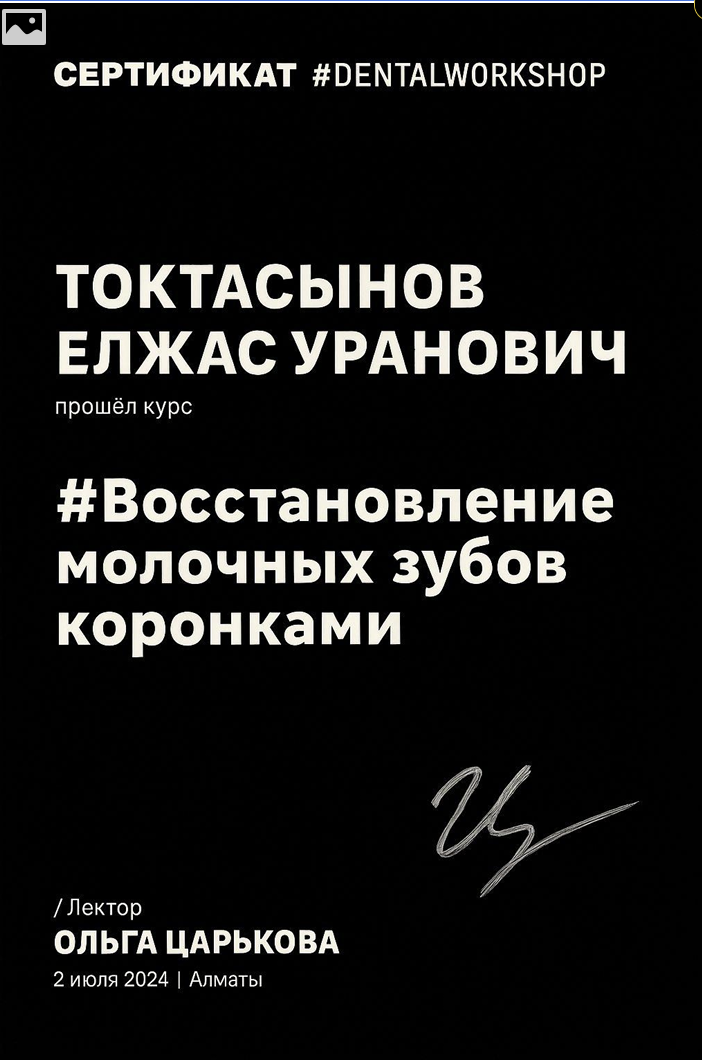

Токтасынов Елжас Уранович

Выпускник Казахского национального медицинского университета им. С. Д. Асфендиярова, интернатура с отличием

Специализация: лечение кариеса, пульпита и периодонтита временных зубов, эстетическая реставрация и профилактика